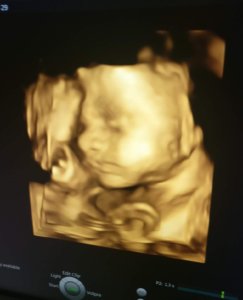

4D babamozi

Ezek a képek nem a babamoziban készültek, hanem az egyik nőgyógyászati vizsgálaton, mobiltelefonnal. Ezeken jobban látszódik a babák arca, mint a babamoziból.

Összességében született pár cuki kép, és az egész fel lett véve videóra is. B magzat jógapózban volt végig, mégpedig olyanban, amire élő ember szerintem nem képes: mindkét lába a fejéhez volt behúzva teljesen, így az arcát nem is láttuk igazán.

Mindent összevetve az emlék miatt megérte.